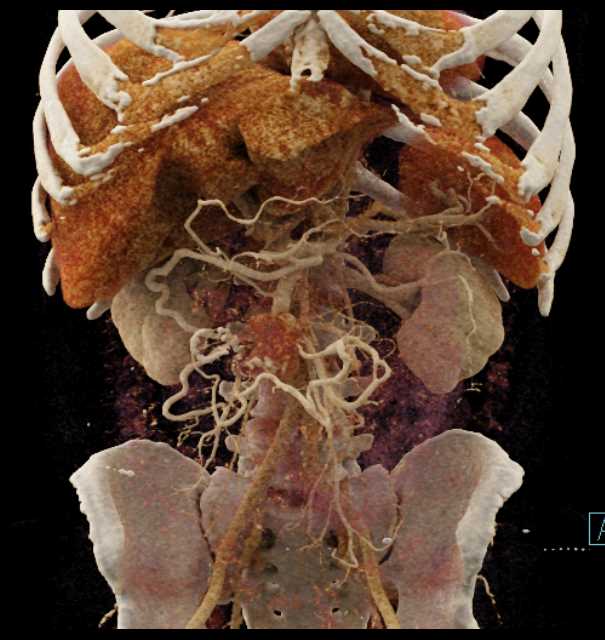

Carcinoid Tumor with Desmoplastic Reaction